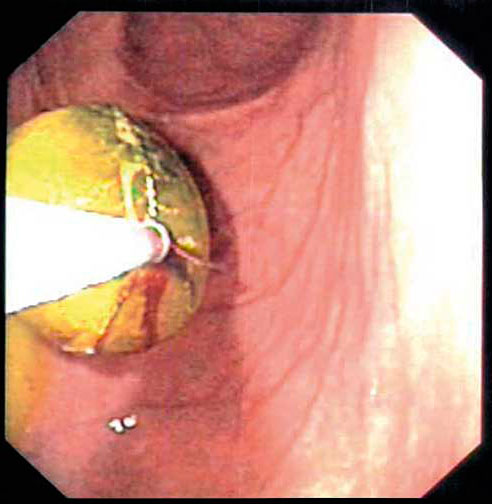

Fallbeskrivning Ovanlig och mycket svår diagnos att ställa